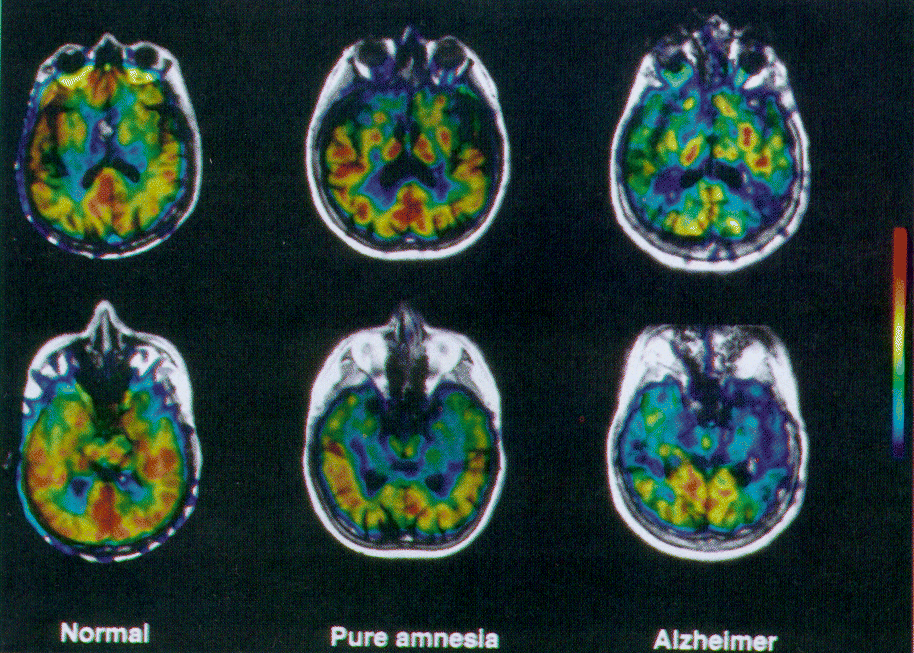

图2。宠物海马纵轴平行平面图像叠加在核磁共振。葡萄糖代谢减少双边纯健忘症患者的海马结构和广告(图片)。在广告中,患者代谢减退也观察到杏仁核和颞顶联合区。颜色栏表示程度的脑葡萄糖代谢率从0到60µmol / 100克/分钟。

宠物的代谢研究。大脑葡萄糖代谢率在内侧颞区显著低于外侧颞区域在正常对照组(表3,图2)。事后测试显示,有一个显著减少CMRGlc外侧颞叶和顶叶皮层在AD患者与正常对照组相比,纯粹的失忆症。

内侧颞区域内,CMRGlc海马头部有点高于正常对照组,但差异不显著。单向方差分析表明显著降低CMRGlc海马在纯粹的失忆症,和杏仁核和海马AD患者的头。

结果:虽然杏仁核和海马结构在纯失忆症没有显著不同于正常人的葡萄糖代谢的头部,海马显著低于纯失忆症。在广告中,患者代谢减退被发现一直延伸到杏仁核,海马头,和parietotemporal皮层,以及amygdalohippocampal萎缩。

结论:海马头功能障碍在失忆症患者记忆障碍中起着重要的作用。进一步代谢障碍amygdalohippocampal系统和周围协会皮层反映了广告的病理生理学。